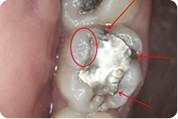

Svima dobro poznati, sivi, amalgamski ispuni, danas se iz zdravstvenih i estetskih razloga zamjenjuju estetskim, kompozitnim ispunima.

Naša su iskustva u praksi da redovno, ispod amalgamskog ispuna, u toku sanacije zuba pronalazimo karijes. Obrazloženje je u činjenici da se amalgam kao materijal za ispun s vremenom skvrčava i time stvara pukotinu između sebe i stjenke zuba. To naravno dovodi do prodora bakterija karijesa u kavitet na zubu a time i kvarenja zuba.

Estetski ( bijeli ) materijali ne mijenjaju volumen tijekom vremena. Dakle, nema pukotine, nema prodora bakterija i nema kvarenja zuba.